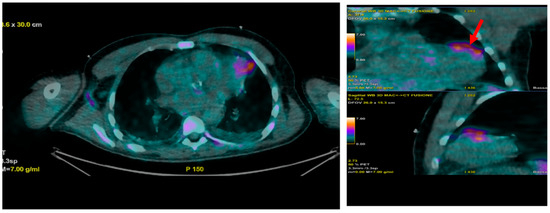

Multimodality Imaging in Infective Endocarditis: A Clinical Approach to Diagnosis

by Leonardo Brugiatelli, Francesca Patani, Carla Lofiego, Martina Benedetti, Irene Capodaglio, Pongetti Giulia, Francioni Matteo, Paolini Enrico, Nazziconi Marco, Kevin Maurizi, Furlani Giulia, Massari Arianna, Luciani Simone, Anselmi Benedetta, Gatti Chiara, Schicchi Nicolò, Fogante Marco, Tarsi Giovanni, Dello Russo Antonio, Di Eusanio Marco, Marini Marco and Fabio Vagnarelliadd Show full author list remove Hide full author list

Medicina 2025, 61(12), 2241; https://doi.org/10.3390/medicina61122241 - 18 Dec 2025

Infective endocarditis (IE) is a life-threatening condition with a rising incidence, demanding rapid and precise diagnosis. While echocardiography remains the cornerstone of initial evaluation, its limitations in complex cases—such as those involving prosthetic valves or cardiac devices—are well-known. This review synthesizes current evidence [...] Read more.

Infective endocarditis (IE) is a life-threatening condition with a rising incidence, demanding rapid and precise diagnosis. While echocardiography remains the cornerstone of initial evaluation, its limitations in complex cases—such as those involving prosthetic valves or cardiac devices—are well-known. This review synthesizes current evidence and guidelines to outline a practical, multimodality imaging approach for IE. We emphasize that integrating advanced techniques like cardiac computed tomography (CT) and [18F]-fluorodeoxyglucose positron emission tomography/computed tomography (FDG PET/CT) early in the diagnostic pathway, particularly in high-risk scenarios, significantly enhances diagnostic certainty, guides therapeutic decisions, and improves patient outcomes. A tailored imaging strategy, driven by clinical presentation and integrated within a multidisciplinary endocarditis team, is paramount for modern IE management. Full article

(This article belongs to the Special Issue Diagnosis and Treatment of Valvular Heart Diseases)

Show Figures

Figure 1